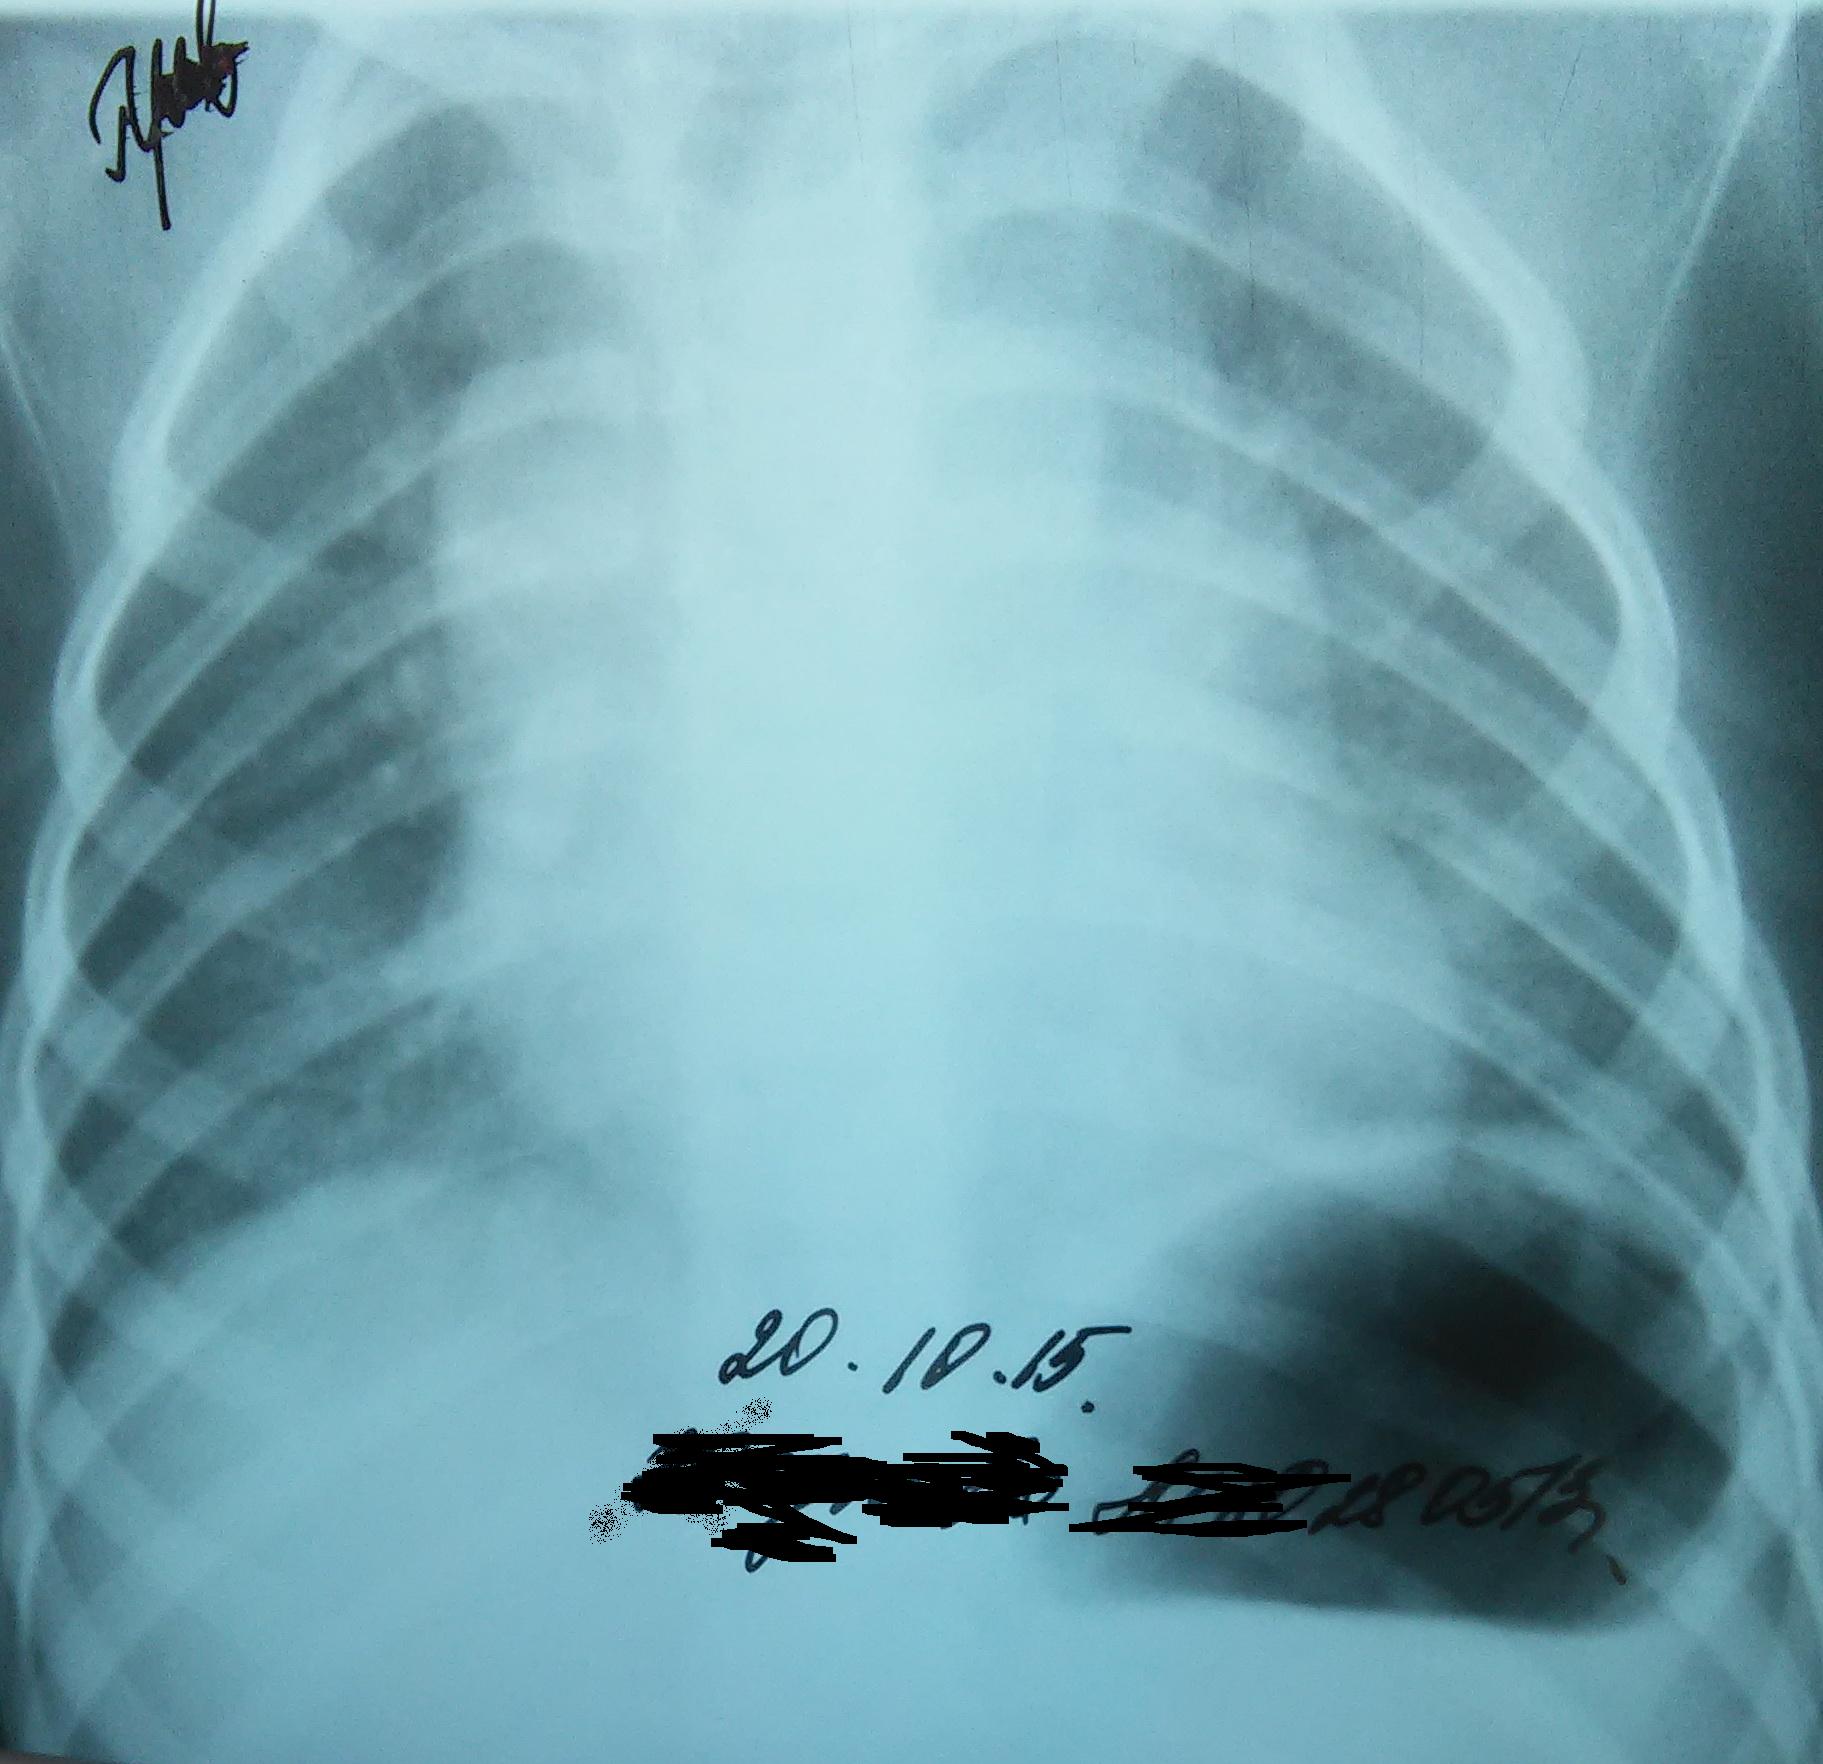

Тимомегалия: что это такое и как проявляется

Раздел: Фотоальбом решений